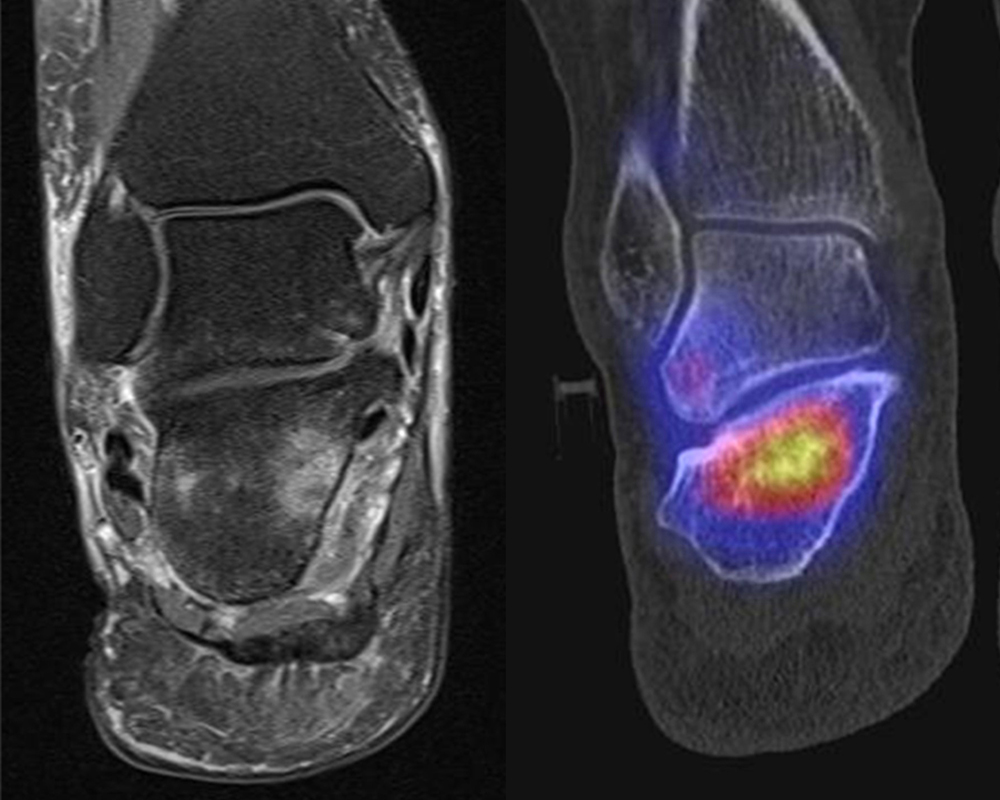

Abbildung 2.1.

Bildbeispiele symptomatische OCL

Zum Lesen der Bildbeschreibung und zur Vollansicht bitte das Bild anklicken. Bild: H. C. Rischke

Abbildung 2.2.

Bilder eines Patienten mit Z. n. mehrfachen Sprunggelenksdistorsionen in der Vergangenheit, besonders heftige Distorsion des linken Sprunggelenkes 5 Wochen vor der Untersuchung. Die SPECT/CT zeigt eine instabile osteochondrale Läsion mit deutlicher Aktivierung.

Abbildung 2.3.

Klärung bei Schmerzen im rechten OSG bei OCL an der medialen Talusschulter. Z. n. OSG-Distorsion vor 2 Jahren und Z. n. OSG-Fraktur / Syndesomosenruptur. Ausgedehnte OCL, hier jedoch kein erhöhter Knochenmetabolismus; lediglich Nachweis einer Stressreaktion im Bereich der Synchondrose eines Os trigonum als Schmerzursache.